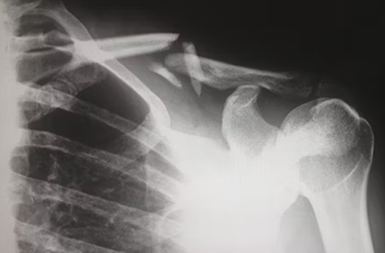

Shoulder

We treat all acute and chronic shoulder problems including rotator cuff tears, shoulder arthritis and shoulder instability or dislocations.